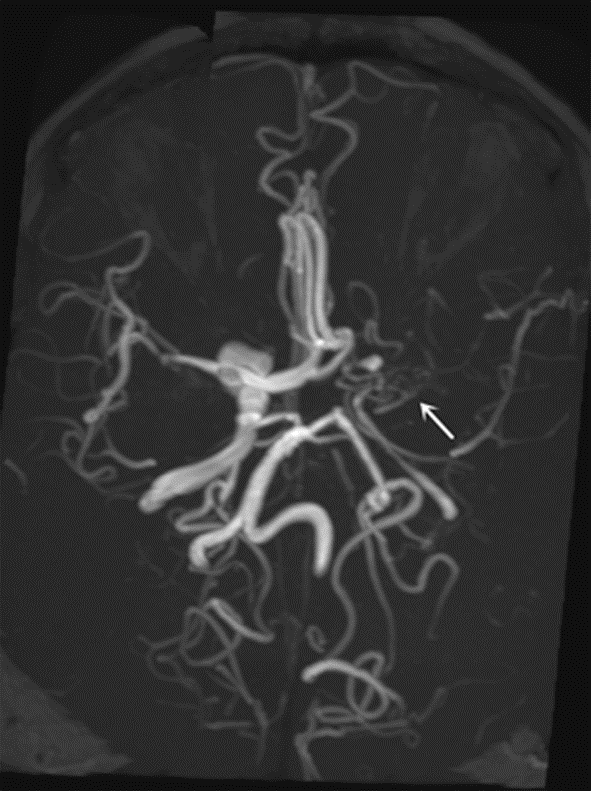

Objective To summarize diagnostic and differentialdiagnostic approaches for initial detection of moyamoya disease (MMD) using carotid ultrasound (CAU). Methods We report two patients who were first diagnosed with MMD by CAU and summarize the diagnostic reasoning and differential considerations. Relevant literature was reviewed to contextualize these findings. Results Case 1: A 57-year-old female presented with a >10 year history of dizziness and headache with recurrence over 3 days. CAU showed a reduced diameter of the left internal carotid artery (ICA), decreased flow velocity, and a lower resistance index, raising suspicion for severe intracranial stenosis or occlusion and prompting clinical exclusion of MMD. Magnetic resonance angiography (MRA) confirmed severe stenosis of the left ICA with absent distal branches and multiple small abnormal vascular networks in the left suprasellar region, consistent with MMD. Case 2: A 23-year-old male presented with dizziness for >1 year and transient right upperlimb weakness for 1 day. CAU and transcranial color Doppler (TCCD) showed a narrowed right ICA with reduced flow velocity and increased resistance index, suggesting chronic occlusion of the right middle cerebral artery and stenosis of the left middle cerebral artery, raising the possibility of MMD. MRA demonstrated an indistinct right ICA and right middle cerebral artery and narrowing of the left middle cerebral artery. On followup, the patient was diagnosed with MMD. Conclusion When CAU reveals a small internal carotid artery diameter accompanied by slowed flow velocity, clinicians should perform a comprehensive evaluation-including TCCD and further vascular imaging-to avoid missed or incorrect diagnoses of MMD.